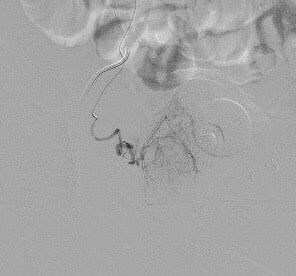

Mô tả lại tiến trình can thiệp, BS Giang vẫn còn cảm thấy hạnh phúc bởi kíp kỹ thuật đã tạo nên một kỳ tích trong lịch sử y học Việt Nam và cũng chưa từng có trong y văn thế giới. “Khi thực hiện nút mạch cho bệnh nhân, sau khi hoàn thành 1 bên hoàn toàn tốt, chúng tôi thực hiện bên còn lại thì gặp khó khăn do 3 gốc động mạch tuyến tiền liệt, động mạch bàng quang dưới, động mạch bàng quang trên được tách ra cùng vị trí của động mạch chậu trong tạo thành ngã tư rất khó chọn lọc vào động mạch tuyến tiền liệt. Sau những phút nỗ lực cực điểm để tiếp cận được nhánh này thì chúng tôi lại còn ngỡ ngàng hơn, khi động mạch tuyến tiền liệt rất bé, ngắn, lại còn xoắn đúng 1,5 vòng. Với sự thành thạo kỹ thuật của kíp can thiệp, cùng với việc sử dụng khéo léo các vi ống thông và vi dây dẫn siêu nhỏ cỡ dưới 0.010”, kíp can thiệp đã thành công để có thể đi qua được “vòng xoắn” đó và tiếp cận siêu chọn lọc động mạch tuyến tiền liệt.

Thời khắc thành công, cả kíp chúng tôi cùng òa lên vui mừng vì đã cứu được bệnh nhân khỏi tình trạng bệnh bí tiểu cấp. Bên cạnh đó, ngay từ khi bắt đầu, chúng tôi đã quyết tâm phải điều trị thật triệt để, giúp cho bệnh nhân đạt hiệu quả cao nhất, không để tái phát. Vì vậy ngoài cách nút tắc động mạch tuyến tiền liệt trong nhu mô bằng hạt thông thường, chúng tôi còn sử dụng keo sinh học để gây tắc hoàn toàn gốc động mạch tuyến tiền liệt hai bên để tránh tái thông nhánh nuôi. Đây là vật liệt khá rẻ nhưng sẵn có, mà hiệu quả điều trị rất cao. Tuy nhiên, khi sử dụng cần bác sĩ rất thành thạo, có kỹ thuật thật tốt để kiểm soát không bị biến chứng cho bệnh nhân, đặc biệt là biến chứng trào ngược gây nhồi máu hoại tử tạng lành như bàng quang và trực tràng. Đây là lần đầu tiên chúng tôi sử dụng kỹ thuật gây tắc “kép” như thế này. Trên y văn thế giới, chúng tôi cũng chưa thấy ghi nhận cách kết hợp độc đáo như vậy.

| Chụp động mạch chậu trong cho thấy động mạch tuyến tiền liệt tách ra từ vị trí khó | Hình ảnh cho thấy động mạch tuyến tiền liệt tách ngay gần động mạch bàng quang trên, dưới đồng thời xoắn 1,5 vòng | Động mạch tuyến tiền liệt sau khi qua được vị trí khó khăn | Chụp mạch kiểm tra lại sau gây tắc hoàn toàn bằng hạt và tắc gốc bằng keo histoacryl |